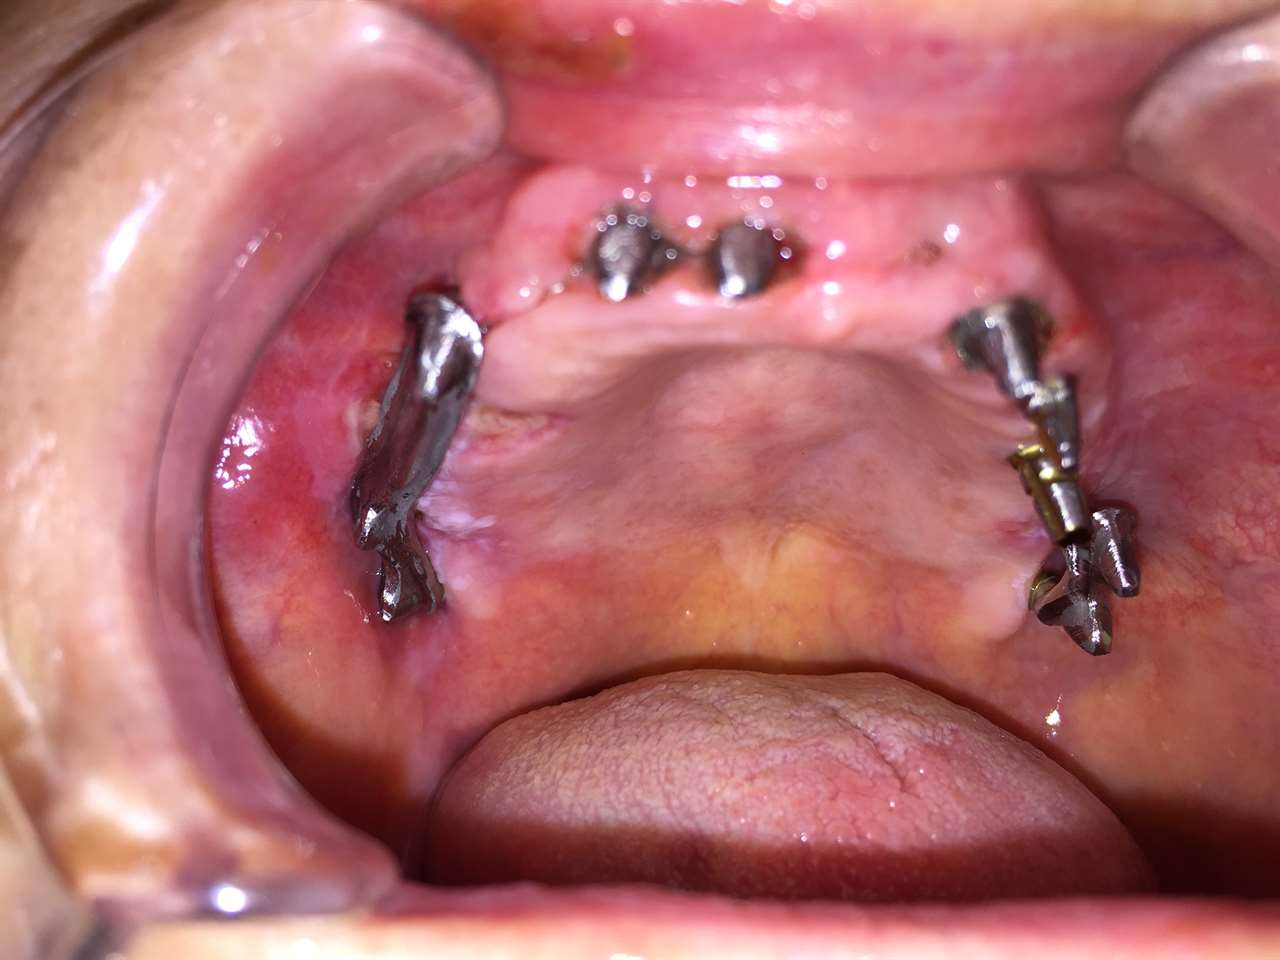

Teljes alsó,felső állcsont helyreállítása azonnal

terhelhető implantátumokkal és porcelán hidakkal.